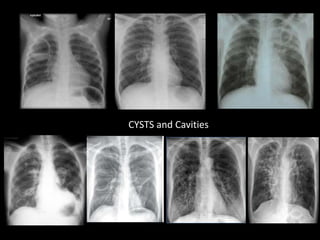

CYSTS and Cavities

Cavities with air fluid level